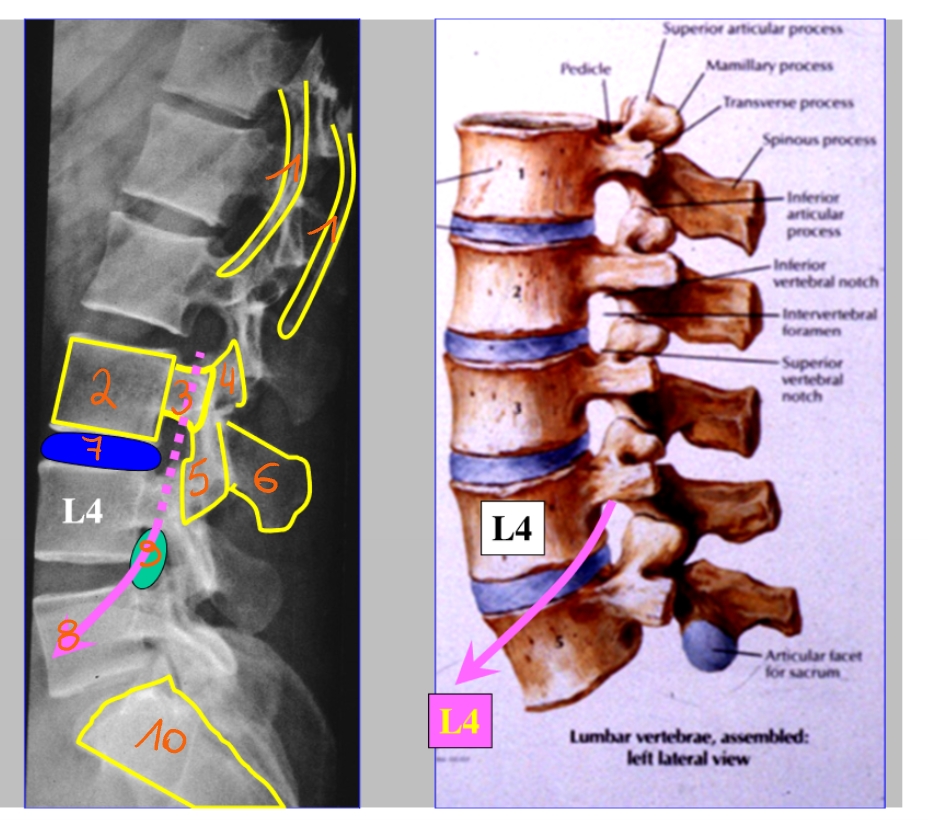

corpus T12

bovenrand van de arcus

processus spinosus

processus articularis inferior

pedikel

corpus L3

corpus L3

pedikel

processus articularis superior

processus articularis inferior

processus spinosus

discus intervertebralis

spinale zenuw L2

foramen intervertebrale

sacrum

linker driekwart/ schuine opname

processus articularis superior

processus transversus

pedikel

isthmus = pars interarticularis

lamina

processus articularis inferior